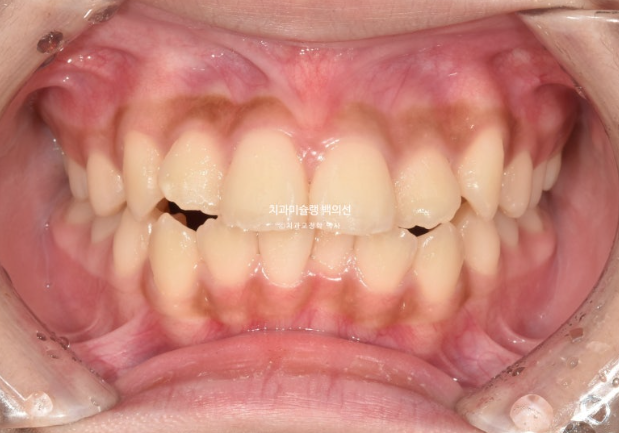

23년 10월 교정치료를 위해 온 중학생 환자입니다.

고치고 싶은 것은 돌출입

덧니도 있고 치열도 삐뚤하여 작은어금니 4개 발치가 필요한 상황입니다.

23.10